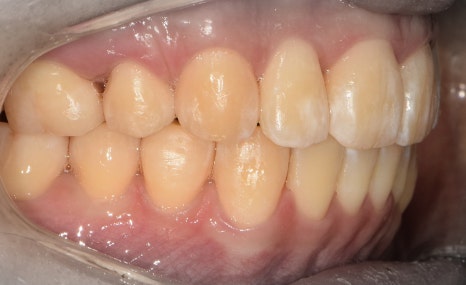

측면에서는 크게 2가지를 느낄 수 있습니다.

- 전치부 치아들의 치축, 전방 뻐드러짐

- 1치대 1치의 관계

*정상이라면, 1치대 2치의 관계를 가져야 됩니다.

또한, 측절치 및 송곳니의 총생들도 같이

관찰을 할 수 있습니다.

앞서, 1치대 1치 관계에 있던 교합관계들이

1치대 2치의 관계로 바뀐것을 볼 수 있으면서

길쭉하게 느껴졌던, U shape 형태의 악궁이

딱 보기 좋은, U shape 로 바뀌었죠.